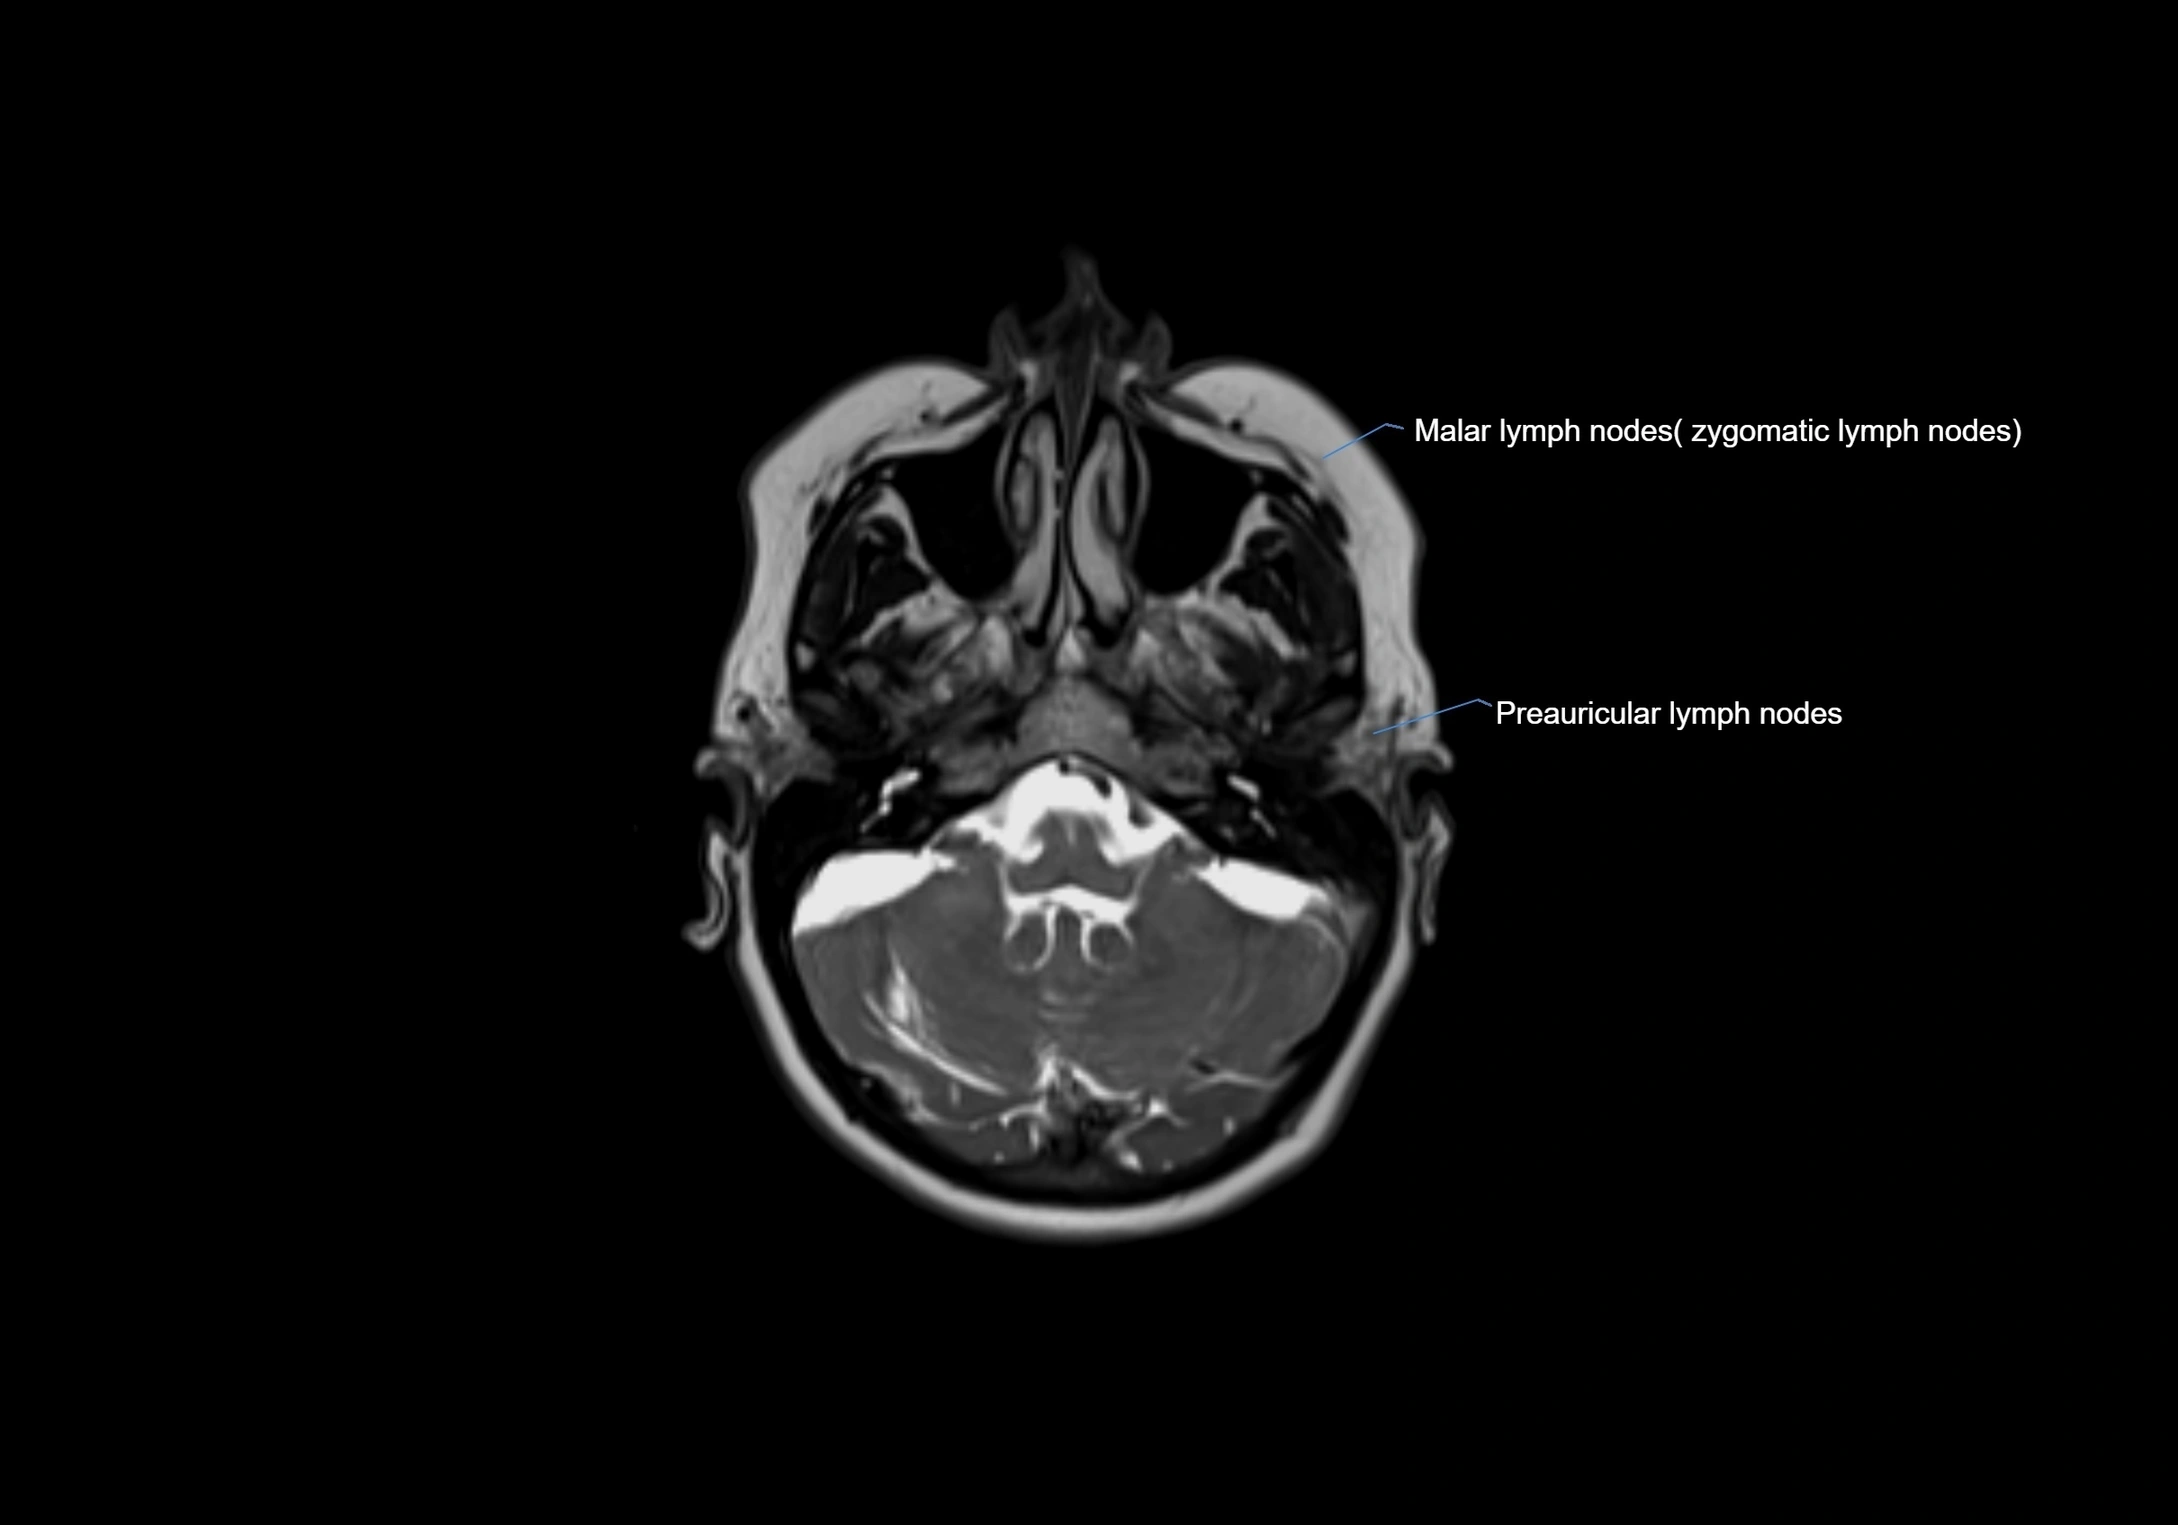

Accessory lymph nodes are small, secondary lymph nodes located along the main facial and cervical lymphatic chains, often adjacent to primary lymph nodes, such as preauricular, submandibular, or occipital nodes. They are typically less than 5 mm in diameter, embedded within subcutaneous fat or connective tissue, and may be variable in number and location. These nodes provide additional filtration and immune surveillance for lymph collected from the face, scalp, and neck regions. Accessory lymph nodes are usually non-palpable in healthy individuals but may enlarge in response to infection, inflammation, or metastasis, making them clinically significant.

• Found along primary lymph node chains, including preauricular, submandibular, parotid, and occipital regions

• Embedded in subcutaneous fat or superficial fascia, often lateral or posterior to primary nodes

MRI Appearance

T1-weighted images:

• Normal accessory nodes appear as small, oval hypointense to intermediate signal structures within subcutaneous fat

• Surrounded by hyperintense fat, enhancing contrast for visualization

• Pathological nodes may appear enlarged or rounded, sometimes with cortical thickening

T2-weighted images:

• Nodes show intermediate signal, with surrounding fat bright

• Useful for detecting edema, inflammation, or infiltration

• Fatty hilum may appear slightly hyperintense relative to cortex